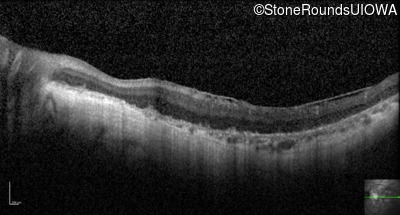

Optical Coherence Tomography - Right - Hand Motion sc

Exemplar / OCT Stack